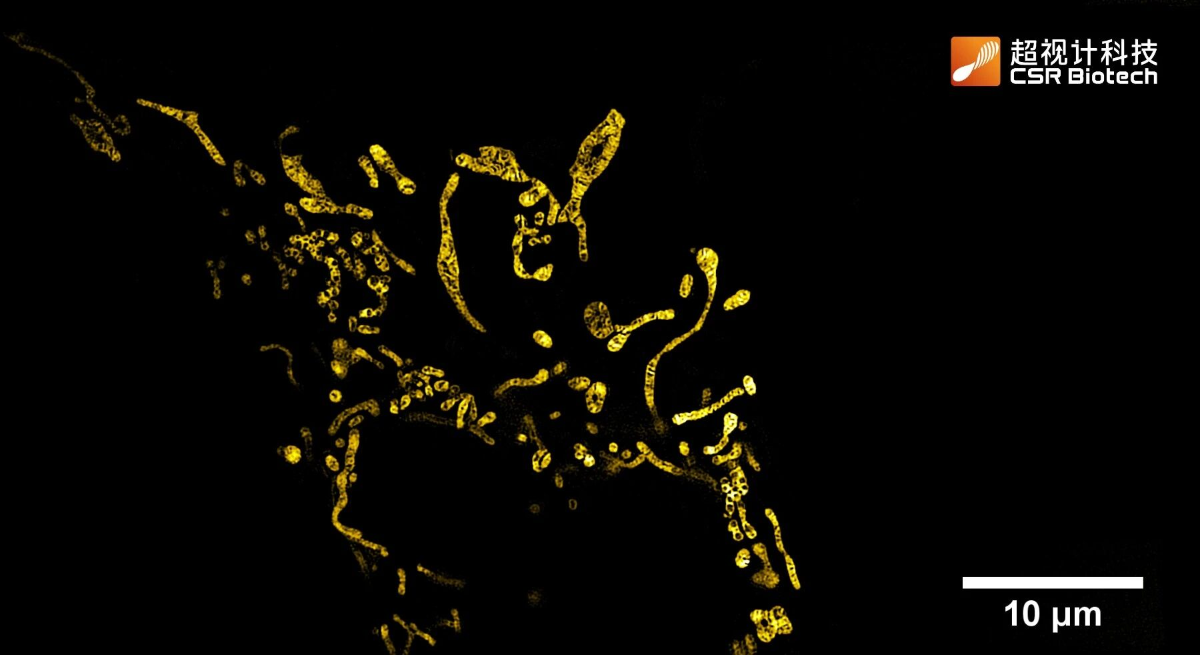

图1 经 Mito-tracker Deep Red 染色后,不同处理组的线粒体形态代表性图像与定量分析结果。比例尺:10μm。

本研究中,借助 HIS-SIM 验证了 DST-3 保护线粒体的依赖机制。OGD/R 损伤后线粒体肿胀、嵴断裂;Homer1 沉默后线粒体碎片化加剧且结构异常更显著;DST-3 处理后线粒体结构更完整。超分辨图像与定量分析均证实,DST-3 能有效改善 OGD/R 诱导的线粒体形态异常,但在 Homer1 沉默后,这种保护效应明显减弱,直接验证 DST-3 对线粒体完整性的保护作用依赖于 Homer1 的介导。

成像样本:线粒体内膜(黄色)